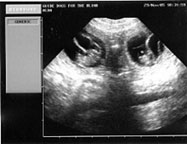

Ultrasound

appointment at GDB. Alda has between 6 and 7 pups. This is just

a guess things can always change.